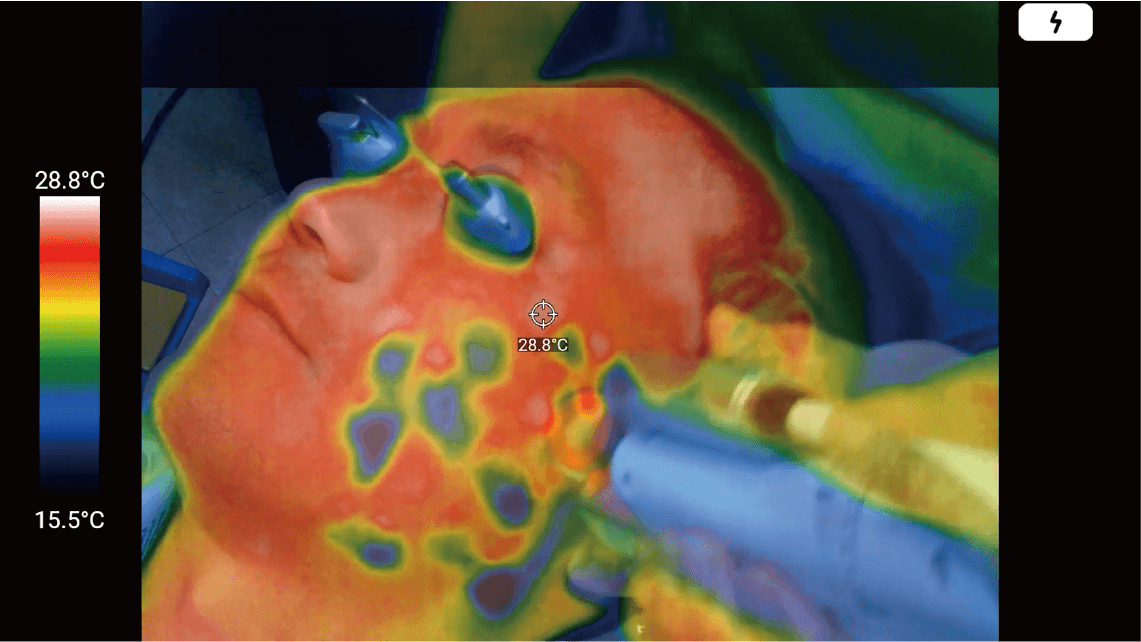

An optimal solution that enables checking the patients’ skin temperature right in front of the eye in real-time when dermatologists use heat-generating equipment such as laser or high frequency on the patients’ skin. Also, you can record and save the treatment video.

Since MetaSCOPE THERMO® accurately measures and displays changes in skin temperature in real-time, dermatologists can directly reflect changes in skin temperature during the procedure. It can recognize the highest/lowest temperature that does not cause injury leading to the maximized treatment result securing perfect patient safety. Until now, the procedure has been performed relying only on the subjective experience of the dermatologist, but now, the use of this solution can dramatically improve the procedure environment.

By wearing MetaSCOPE THERMO®, dermatologists can perform procedures while accurately checking skin temperature, increasing the accuracy of the procedure and ensuring patient safety.

Prevention of injury by detailed management

of the patients’ skin temperature

(burns, frostbite, blisters, etc.)

MetaSCOPE THERMO® guarantees the accuracy of the entire procedure, including before and after the procedure, and the accuracy of the procedure related to temperature minimizes potential side effects such as burns or frostbite that may occur on the skin due to mismanagement of the temperature.